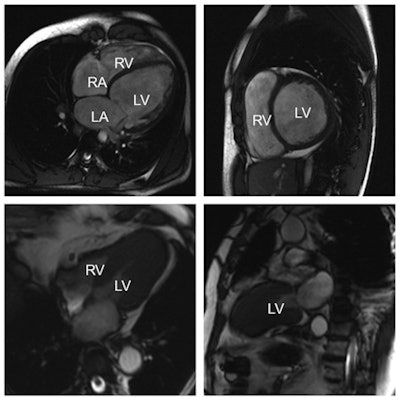

Top row: Example of a dilated cardiomyopathy (DCM). Cine-MR images in four-chamber view (left) and short-axis view (right) at end-diastole show significant dilatation of the left ventricular cavity. Ejection fraction was less than 35% in this patient. (RA = right atrium; LA = left atrium; RV = right ventricle; LV = left ventricle). Bottom row: Example of an asymmetrical, apical hypertrophic cardiomyopathy (HCM). Cine-MR images in a four-chamber (left) and two-chamber view (right) in systole show a markedly thickened left ventricular myocardium predominantly of the apex, as compared with the basal segments. All images courtesy of Dr. Konstantin Nikolaou.MRI can also be crucial in diagnosing congenital heart diseases, in cases in which ultrasound proves inconclusive. But the problem with MRI in cardiac imaging remains its availability; often limited to universities or dedicated centers, and often with long waiting lists. Congenital diseases are usually assessed in babies or very young children, for whom it is almost impossible to lie still for an MRI for 45 minutes without sedation or general anesthesia, which can present a risk for children. Consequently, radiologists may choose to use CT in younger patients, as it offers rapid diagnosis and has become safer in recent years, with a significant improvement in dose reduction strategies.